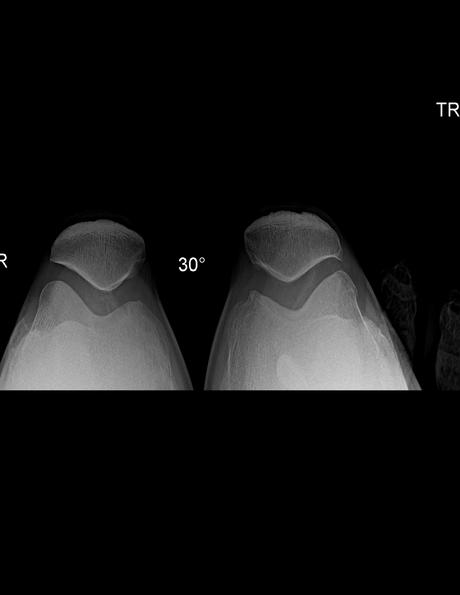

RADIOGRAFIA AP, LATERAL Y AXIALES DE RODILLAS

Se identifican las estructuras óseas de rodillas fémur distal, tibia, peroné proximal y rotula con adecuada mineralización, sin evidencia de fractura. Existe material por artroplastia nivel de tibia izquierda, así como área de atomización en parte distal de fémur izquierdo.

Rotulas tipo II de Wiberg.

Los espacios articulares patelofemorales, derecho con disminución leve de su amplitud de izquierdo con adecuada amplitud.

-Angulo Muñiz derecho de 6.7 ° e izquierdo de -12.7 °

-Ángulo patelofemoral, ambos con vértice medial.

Angulo intercondileo derecho 105.3° e izquierdo 106.5 °

Angulo de congruencia derecho – 11.2 ° e izquierdo de -7.1 °

EN EL PRESENTE ESTUDIO RADIOGRÁFICO, EXISTE DESPLAZAMIENTO LATERAL DE RÓTULA IZQUIERDA.